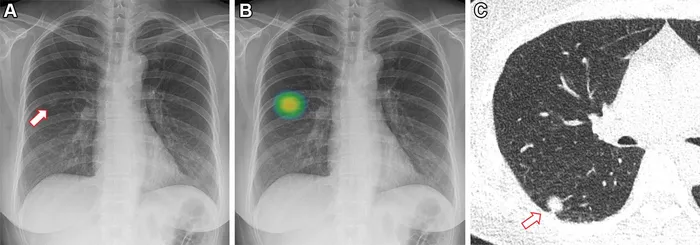

- Detection & Localization:

- Identifies pathologies: lung nodules, fractures, intracranial bleeds.

- Aids in Computer-Aided Detection (CADe).